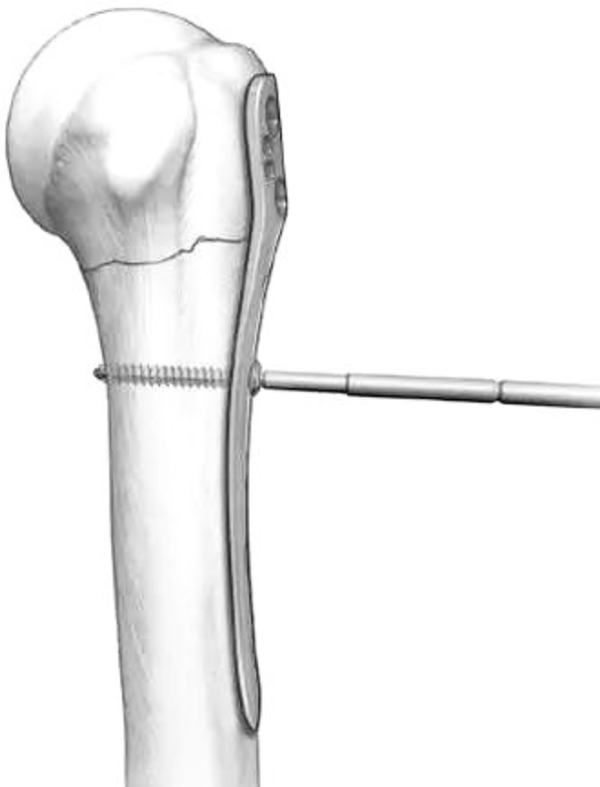

图13 肱骨距螺钉固定

2、注意肱骨距的修复与重建,肱骨头骨折块复位不佳存在内翻移位或肱骨距骨缺损,肱骨没有很好地重建内侧的支撑,导致继发性的复位丢失或内固定断裂。可以采用髓腔内结构性植骨以重建内侧支撑。如果内侧皮质结构尚完整,可以使用肱骨距螺钉斜跨干端与后内侧皮质以行支撑。